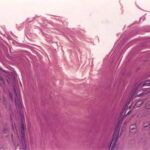

Pathologic findings in pityriasis rubra pilaris vary according to the duration of the disease. The findings are most likely to be diagnostic in the acute phase, when hyperkeratosis, acanthosis with broad short rete ridges, and alternating orthokeratosis and parakeratosis oriented in both horizontal and vertical directions can be observed (see Pityriasis Rubra Pilaris At a Glance). Usually, there is a sparse superficial, perivascular lymphocytic infiltrate in the underlying dermis. Keratinous plugs of the follicular infundibula as well as perifollicular areas of parakeratosis may also be present. A prominent granular layer and dilated, but not tortuous, capillaries are features that help to distinguish pityriasis rubra pilaris from psoriasis, the most important differential diagnosis.